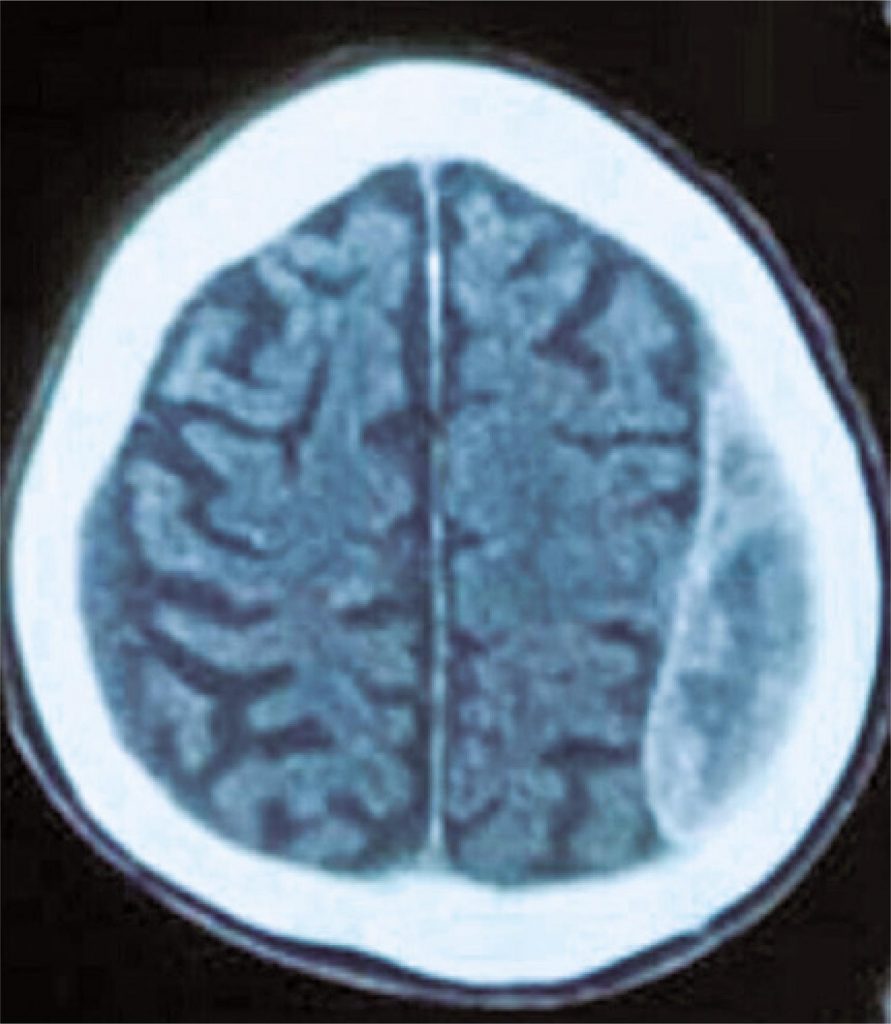

Indivíduos com alto risco de sangramento correspondem à parcela significativa de pacientes submetidos à angioplastia coronária. O tempo ideal de terapia antiplaquetária dupla para esses pacientes ainda permanece incerto, podendo ser auxiliado por escores de estratificação de risco para complicações hemorrágicas e isquêmicas, como o PRECISE-DAPT e o DAPT. Relatamos o caso de um paciente octagenário com conhecido elevado risco de sangramento (PRECISE-DAPT = 65; DAPT = 0) diagnosticado com dois hematomas subdurais crônicos 4 semanas após realização de angioplastia com implante de stent farmacológico para tratamento de doença arterial coronariana. A partir de evidências mais recentes da literatura sobre o manejo de agentes antiplaquetários nesse grupo de pacientes, optou-se pela suspensão precoce do clopidogrel no 31º dia após a angioplastia com evolução clínica favorável ao longo de 24 meses de seguimento.